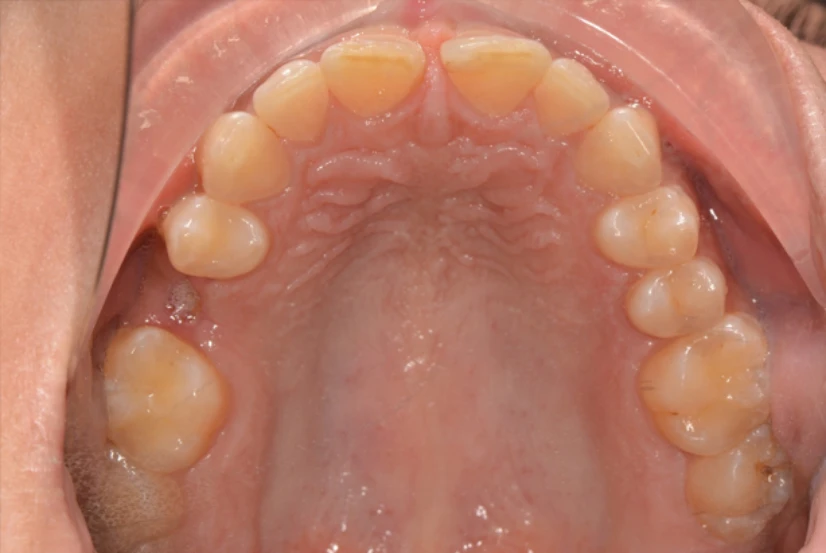

The 15 was broken down significantly and allowed the 14 and 16 to move into the space. In particular, we can see the mesio-lingual rotation of the 16 around the large palatal root. The patient was referred for space regaining following the extraction of 15 root.

A brief 6 month treatment plan with fixed appliances, included an upper labial frenectomy and space closure of the diastema. De-rotation of the 16 and alignment created adequate space for the dentist to place an implant. A fixed retainer for 11-21 was placed and a Hawley retainer with pontic for 15 was provided for use during the implant healing time.